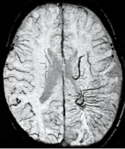

An SWI venogram of a neonate with Sturge-Weber syndrome who did not display neurological symptoms is shown to the left. The initial conventional MR imaging methods did not demonstrate any abnormality. The abnormal venous vasculature in the left occipital lobe extending between the posterior horn of the ventricle and the cortical surface is clearly visible in the venogram. Due to the high resolution even collaterals can be resolved.